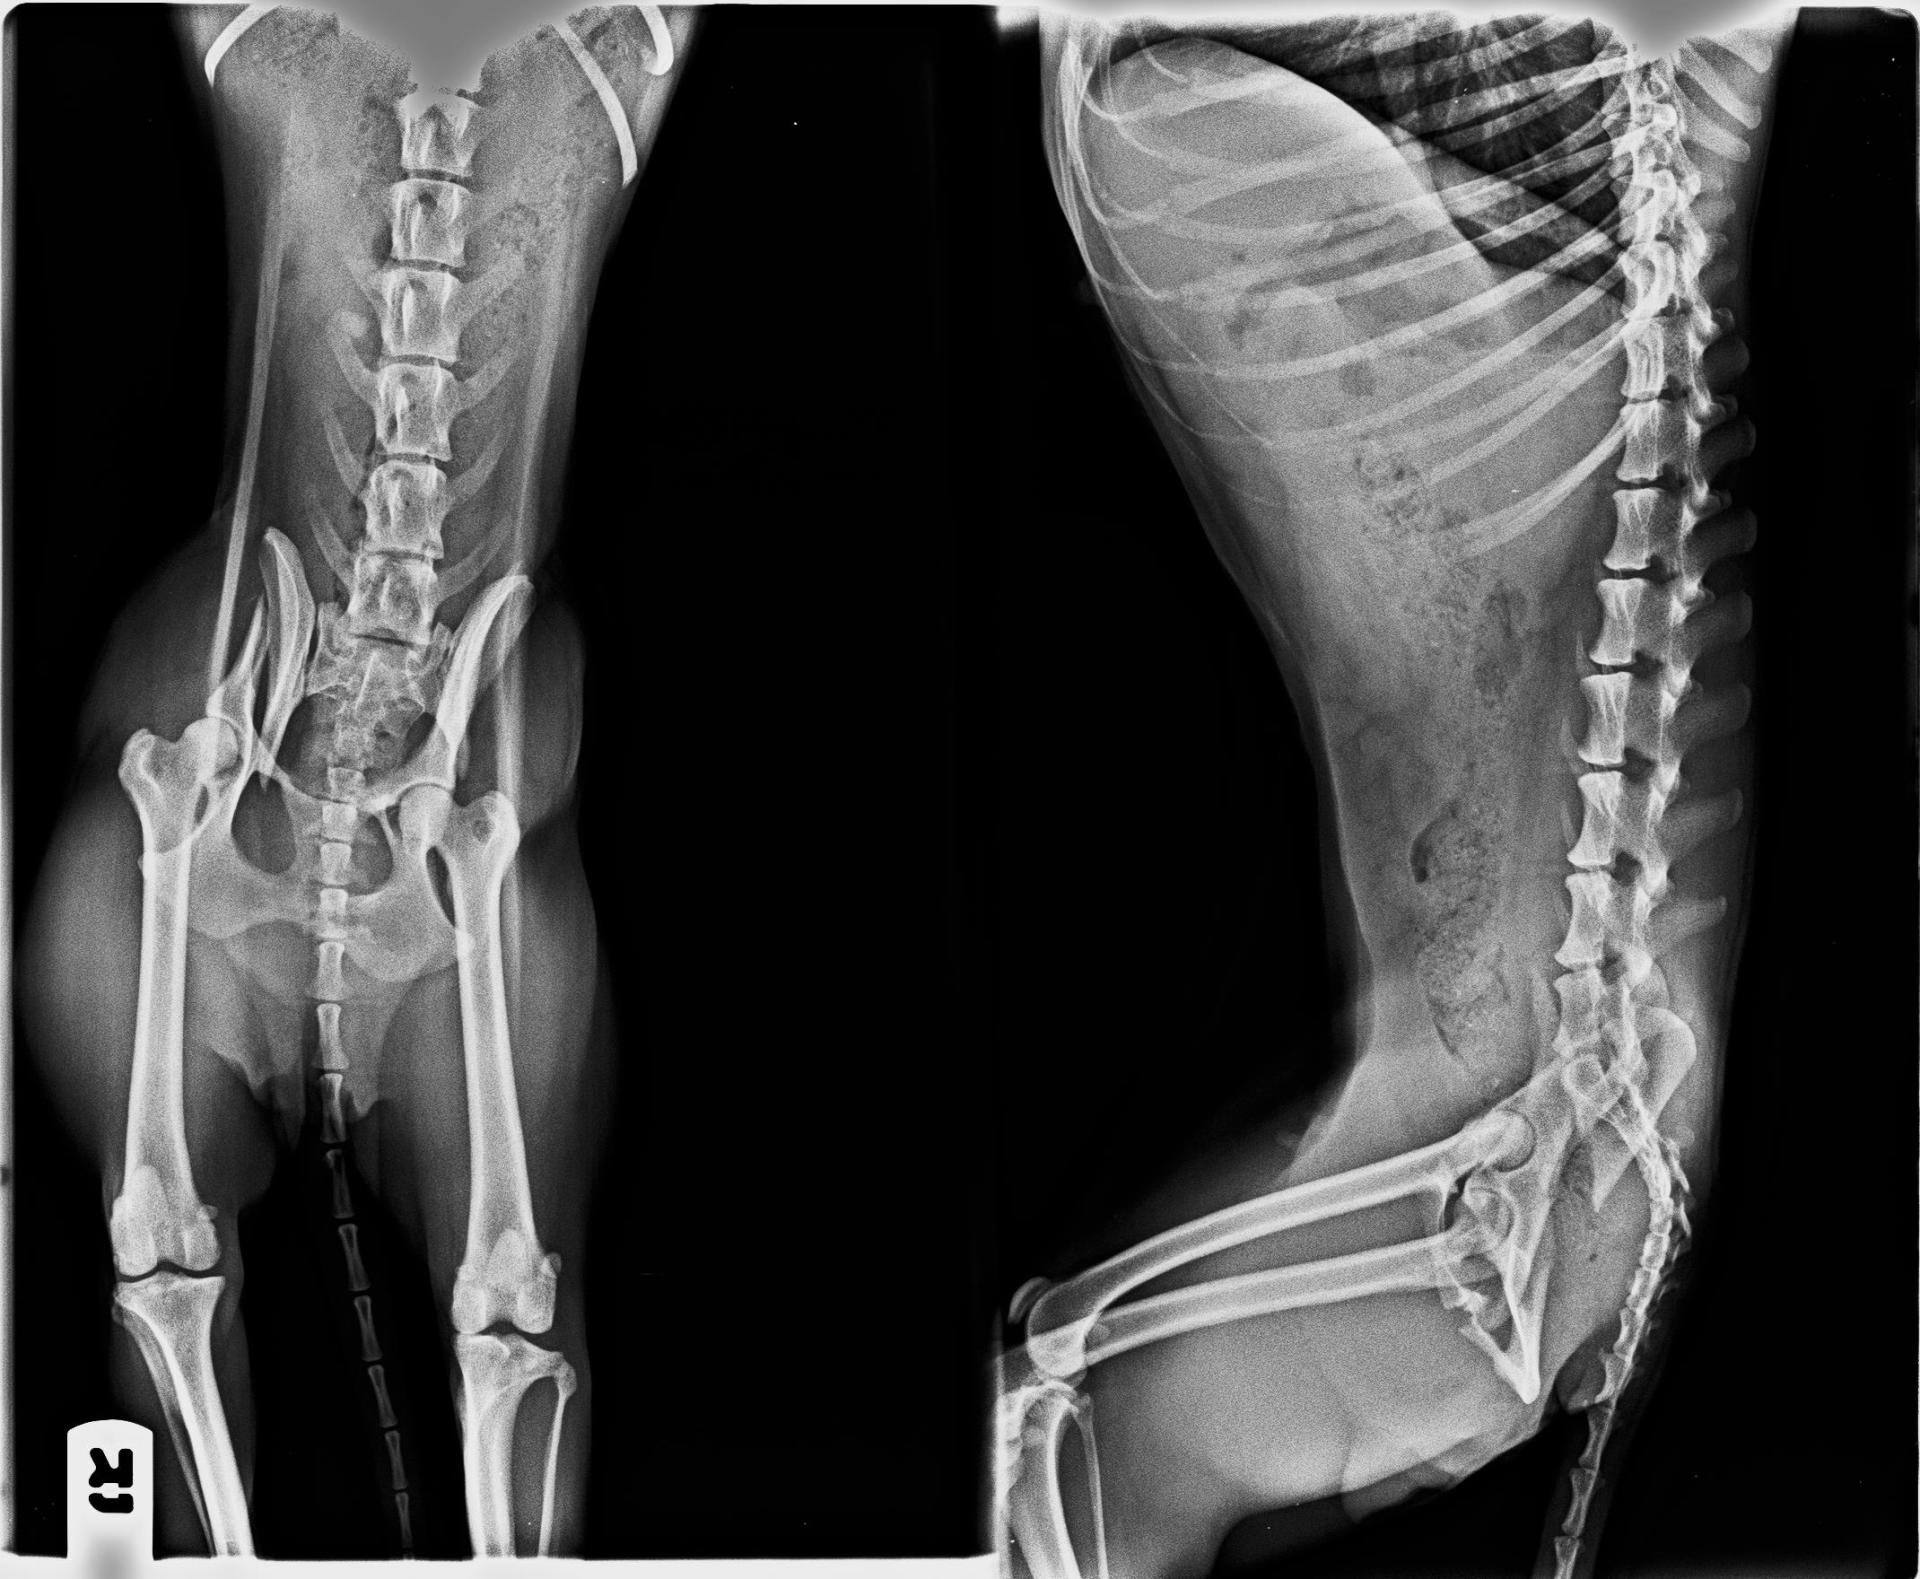

Kary apareció en un municipio de Madrid, una persona la encontró en la carretera, nos pidió ayuda para ella, pero se le olvido mencionar que no apoyaba las patas traseras, (podría haberse operado mucho antes, pero en lugar de eso estuvo varios días hasta que nos la trajo y la vimos, con mucho dolor y sin operar).